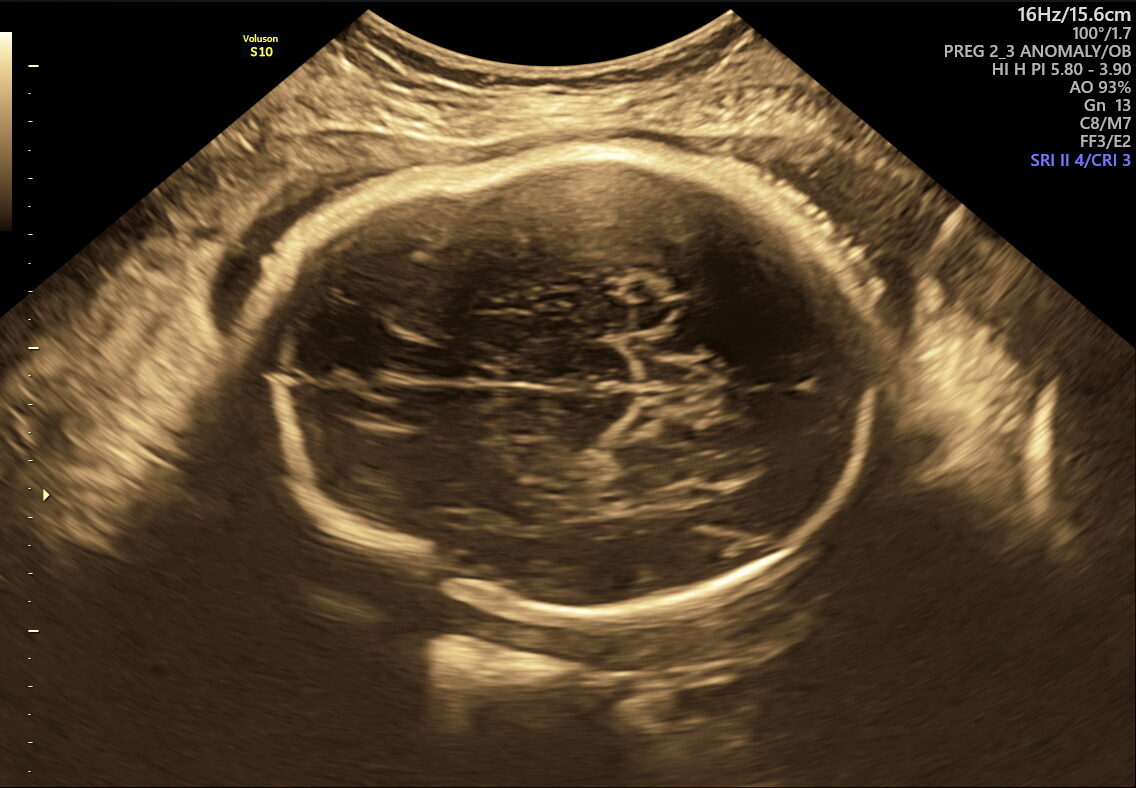

As your pregnancy journey enters its final weeks, NESA Institute of Fetal Medicine offers the Fetal Well-being Scan—a specialized ultrasound performed between 28 and 40 weeks. This essential check ensures your baby’s health and readiness for birth, giving you and your family confidence and clarity as you approach delivery.

This scan is designed to assess multiple aspects of your baby’s well-being and the mother’s preparedness for labour. Here’s what it covers:

- Vital Functions: Measures movements, breathing, and heart rate to make sure your baby is thriving.

This scan focuses on confirming birth readiness and spotting sudden issues that may arise close to your due date. It includes detailed Doppler studies to check blood flow in the umbilical cord and brain, ensuring your baby gets enough oxygen and nutrients.